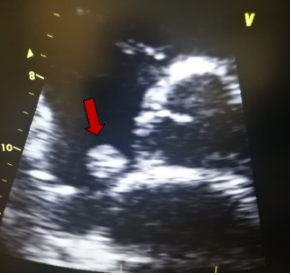

Γενικά, το διαθωρακικό υπερηχογράφημα (ακολουθείται σε μερικές περιπτώσεις από το διοισοφάγειο) είναι η πρώτη διαγνωστική εξέταση. Οι καρδιακοί όγκοι μπορεί να είναι ενδοκοιλοτικοί ή ενδομυοκαρδιακοί (ενδοτοιχωματικοί). Η ηχοκαρδιογραφία απεικονίζει τους ενδοκοιλοτικούς όγκους ως μία πυκνή υπερηχογενή μάζα ακίνητη με ευρεία βάση ή κινητή με μίσχο, που είναι προσαρτημένη στο ενδοκάρδιο. Αντίθετα, οι ενδοτοιχωματικοί όγκοι εμφανίζονται ως μία τοπική πάχυνση του μυοκαρδιακού τοιχώματος μίας κοιλίας. Οι καρδιακοί όγκοι μπορεί επίσης να προβάλλουν το περικάρδιο, με ή χωρίς συνύπαρξη περικαρδιακής συλλογής.

Στην ηχοκαρδιογραφία, το μύξωμα έχει την εμφάνιση μίας ανομοιογενούς κινητής μάζας, συχνά περίπου σφαιρικής, διαμέτρου συνήθως 4-8 cm, με λεία ή με λοβωτή (που φέρει μικρά τόξα στο περίγραμμά της) επιφάνεια. Η μάζα είναι προσαρτημένη στην ενδοκαρδιακή επιφάνεια (συνήθως στο μεσοκολπικό διάφραγμα) με στενή βάση, δηλαδή μίσχο. Σε κάποιες περιπτώσεις μπορεί να συνδέεται στο μεσοκολπικό διάφραγμα με ευρεία βάση. Η ηχογένεια τους δεν είναι ομοιογενής και μπορεί να περιλαμβάνουν υπόηχες περιοχές και σε κάποιες περιπτώσεις ασβεστώσεις. Τα πολυποειδή μυξώματα είναι μεγαλύτερα με λεία επιφάνεια και περιλαμβάνουν υπόηχες και κυστικές περιοχές λόγω εστιών αιμορραγίας και νέκρωσης εντός του όγκου . Τα θηλοειδή μυξώματα τείνουν να είναι μικρότερα και έχουν πολλαπλές λαχνοειδείς προσεκβολές. Αυτός ο υποτύπος σχετίζεται με εμβολικά φαινόμενα. Η θεραπεία ενός καρδιακού μυξώματος είναι η ριζική (πλήρης) χειρουργική αφαίρεση του όγκου.